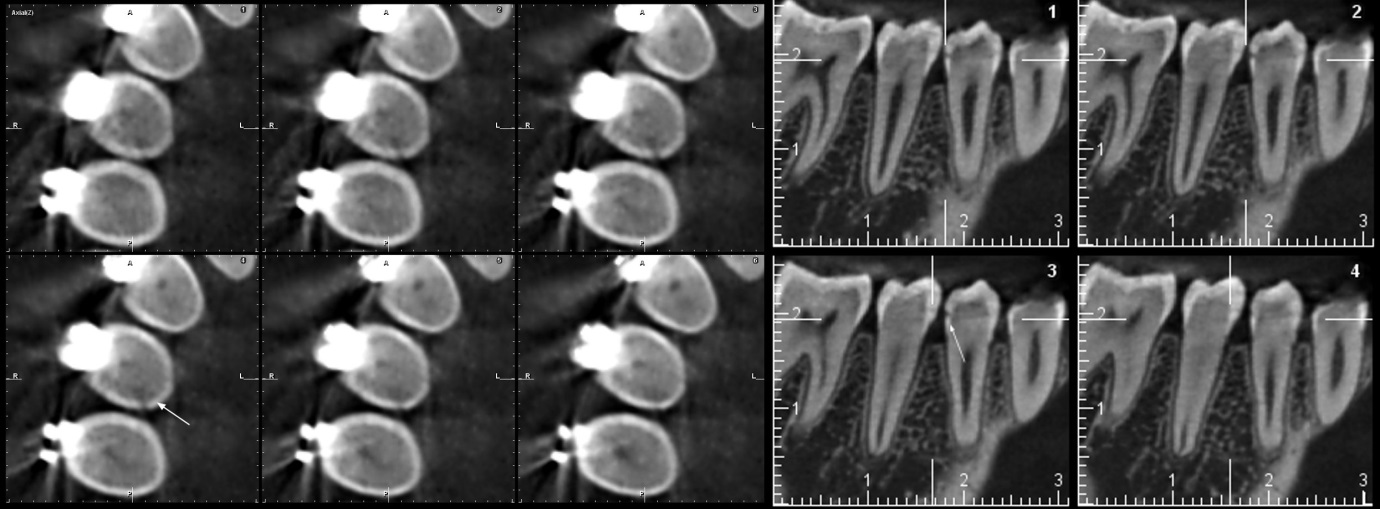

Se presenta la radiografía panorámica (2016) de una paciente femenina de 7 años de edad con un defecto de RIPE en el germen de la pieza 44, de localización distal y profundidad menor a ⅓ de la altura dentinaria (grado I) (figura 2). En la THC adquirida en 2022, con un tamaño de vóxel de 0,15 mm, se observó un defecto hipodenso en forma de fosa, localizado en el esmalte y la dentina (grado I) del tercio medio de la superficie distolingual (figura 3).

Se muestra la radiografía panorámica de una paciente femenina de 8 años de edad. Se observa la presencia de un defecto de RIPE en el germen dentario de la pieza 44, localización mesial y profundidad dentinal de grado I (figura 4). En la THC adquirida, con un tamaño de vóxel de 0,15 mm, se observó un defecto hipodenso de esmalte y dentina (grado I) ubicado en la vertiente mesial de la cúspide lingual (figura 5).